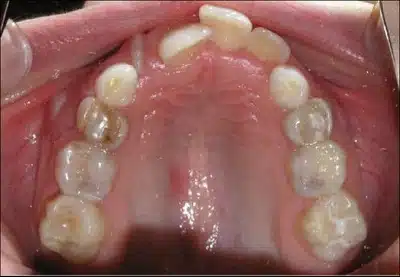

Crowding

Crowding is a common cause of class I malocclusion. It happens when the jaws are placed correctly but the teeth are still crowded, irregular, or poorly spaced. Crowding may be caused by a lack of sufficient space due to large teeth, an excess in the number of teeth, or a combination of both. This orthodontic problem can lead to the wrong eruption of permanent teeth, aesthetic concerns, and cleaning difficulties.